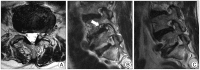

Methods: Over a period of a year, retrospective medical record review and lumbar magnetic resonance images were performed on 32 patients with RLS in spine clinic who were diagnosed by National Institutes of Health criteria. Affected limbs were classified as five. Two grading systems were used in the evaluation of neural compromises.

Results: The incidence of RLS was 5.00% (32/639). There were 16 males (50%) and 16 females (50%). The median age at diagnosis was 55.4 years (range, 25-93 years). There are no correlation between the affected limbs of RLS and neural compromises on the lumbar spine.